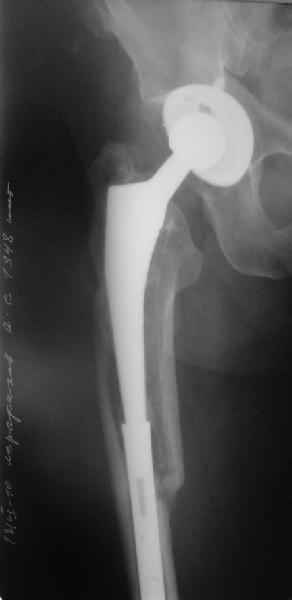

[Ortho] Перипротезный перелом

Пациента удалось осмотреть недавно. Достигнутый результат сохраняется.

Перелом бедра сросся. Конечность опорная и безболезненная, ходит без

трости. Ножка, похоже, реинтегрировалась, как и надеялись.

Снимки и фото в приложении.

Надо ли что-то делать дальше, как полагаете? Убрать винты? Убрать

"удлинитель ножки"? Или оставить все, как есть? Спасибо заранее.